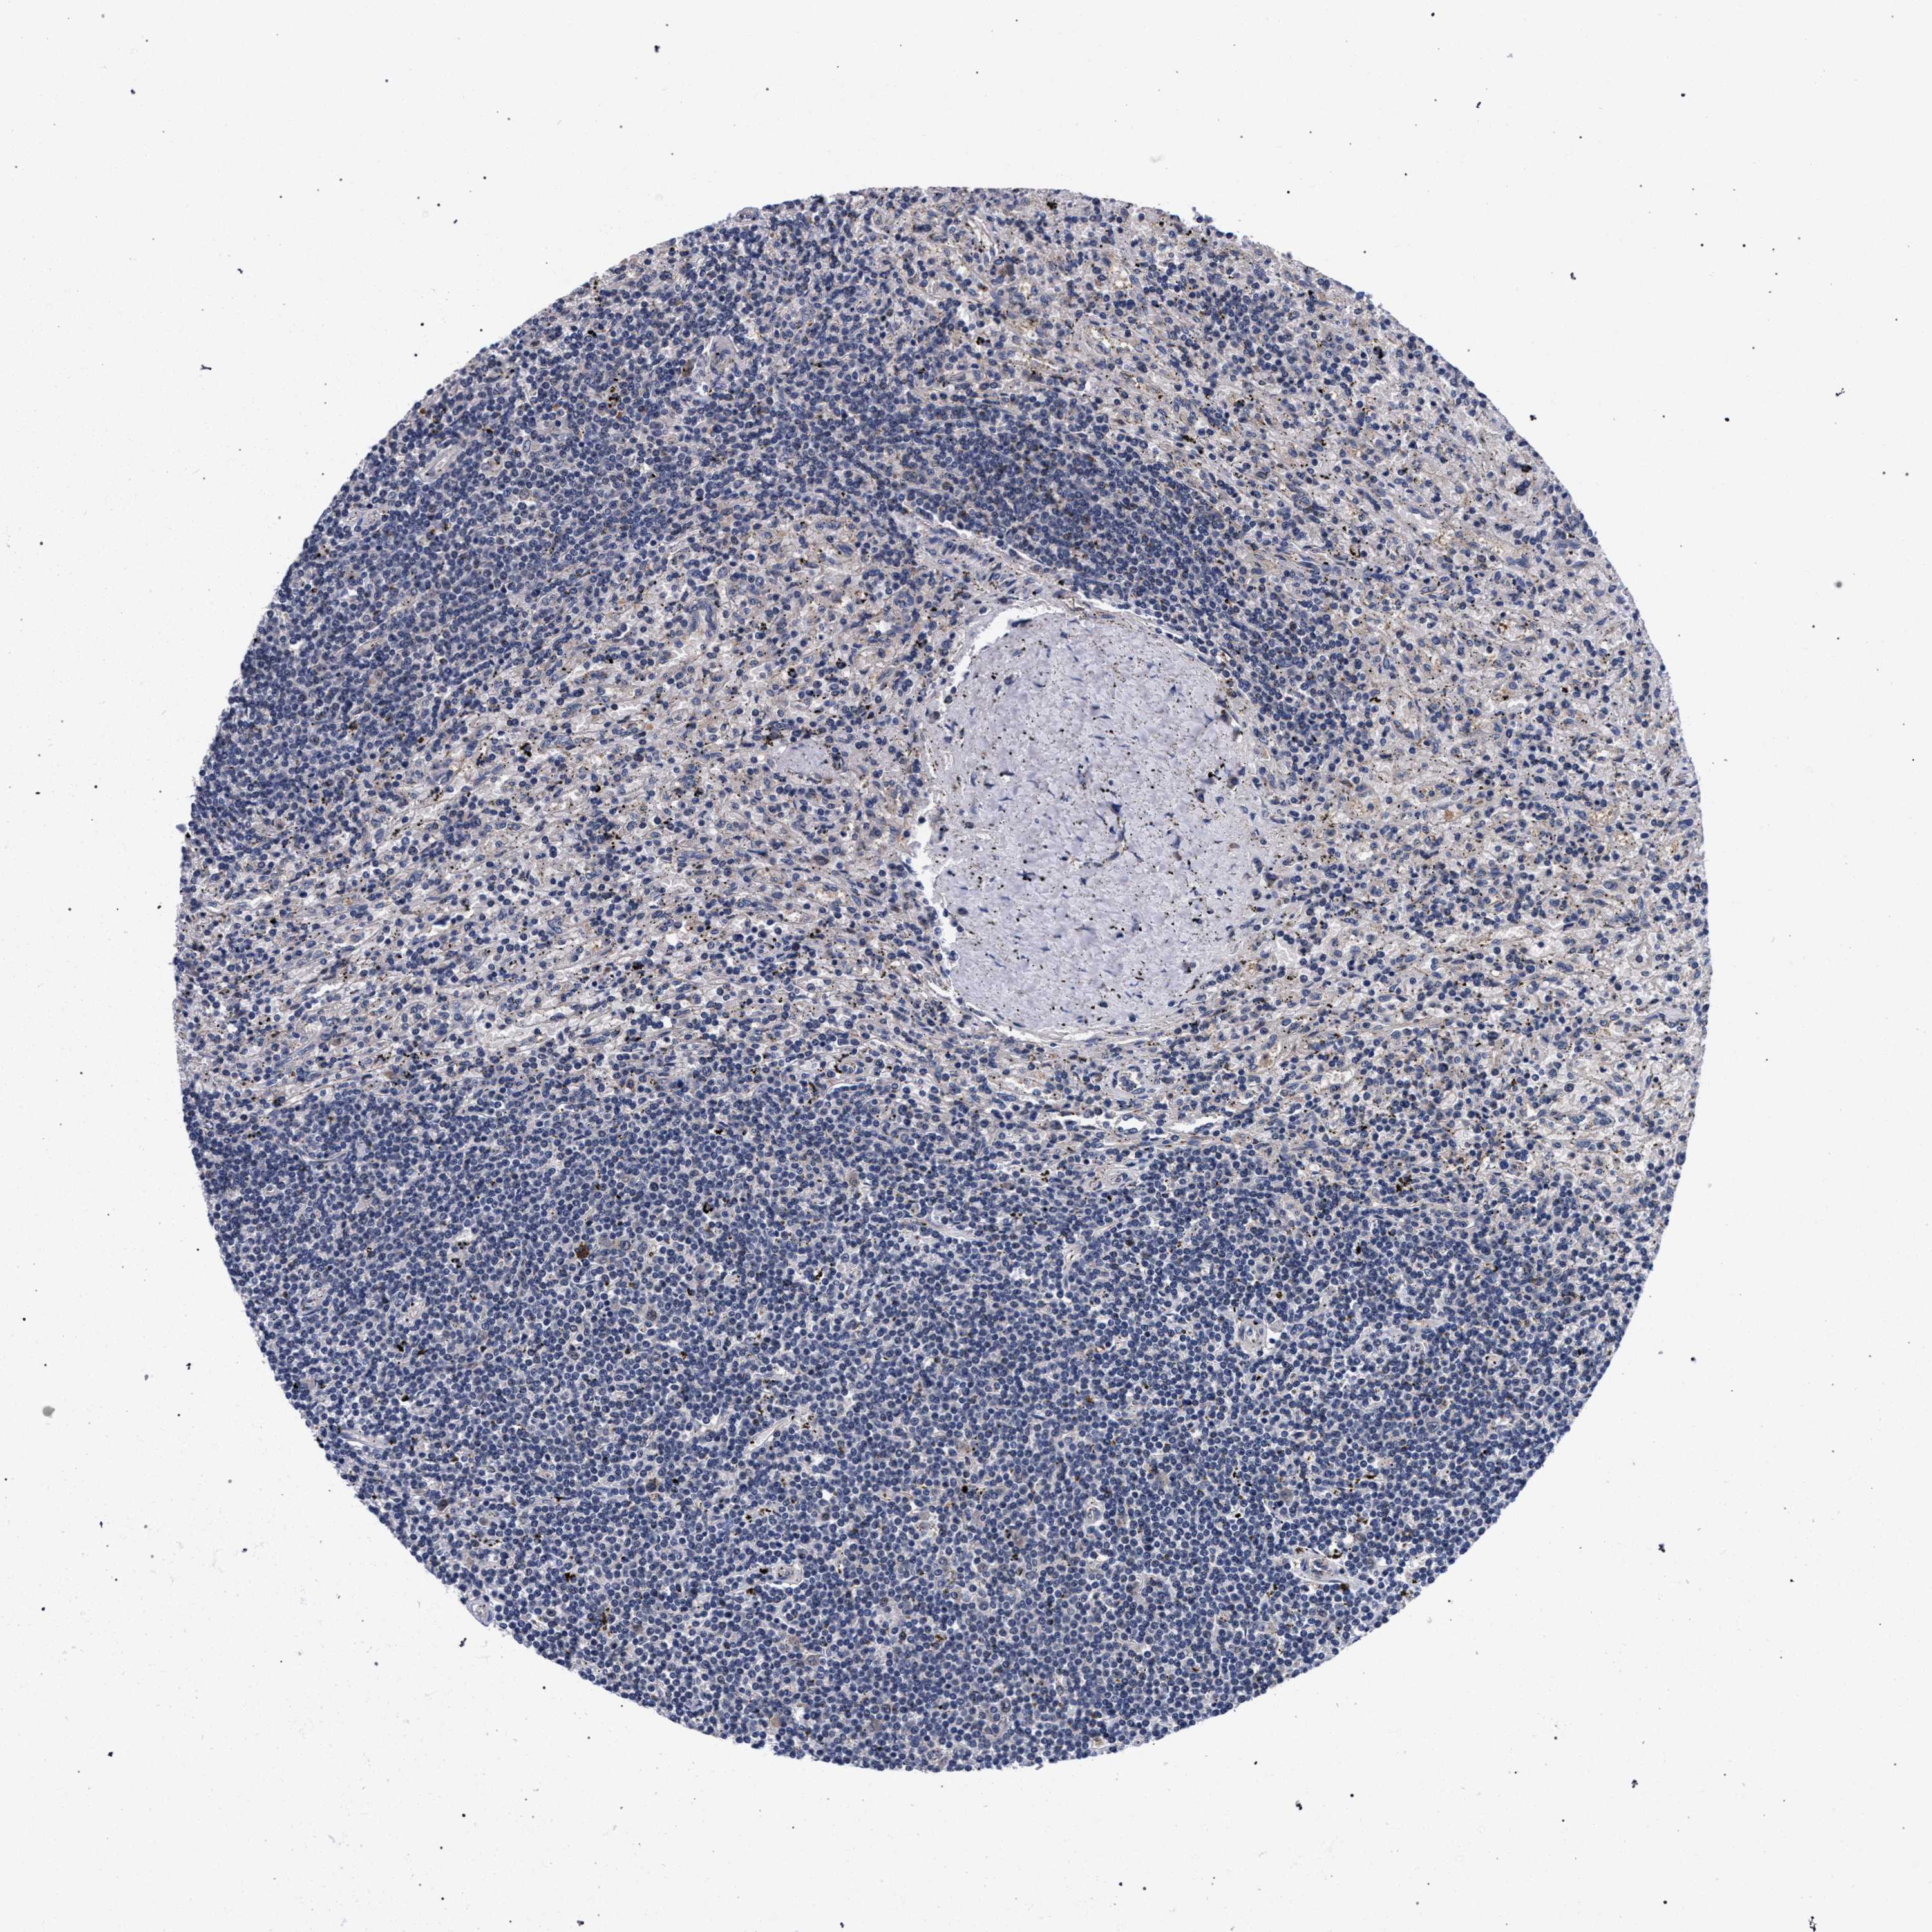

CANCER LYMPHOMA Show tissue menu

LYMPHOMA - Protein expressioni

A mouse-over function shows sample information and annotation data. Click on an image to view it in a full screen mode. Samples can be filtered based on level of antibody staining by selecting one or several of the following categories: high, medium, low and not detected. The assay and annotation is described here.

Each image is clickable and will lead to virtual microscopy that enables deeper exploration of all samples and also displays staining intensity scores, fraction scores and subcellular localization as well as patient and tissue information for each sample.

Antibody HPA019232

Antibody HPA021497

Antibody HPA021768

Hodgkin's disease, NOS

Malignant lymphoma, non-Hodgkin's type, High grade

Malignant lymphoma, non-Hodgkin's type, Low grade